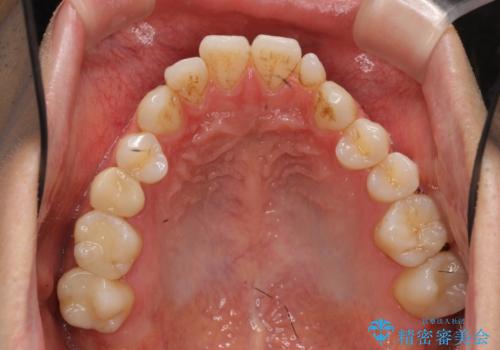

前歯の矮小歯 奥歯の反対咬合 をインビザラインで

- 上下の前歯が気になり来院。

左上2が矮小歯で小さく、また、左の奥歯が反対咬合になっていました。

左上2番はセラミッククラウンで反対側と同じ大きさにしました。

今回は下の前歯を1本抜くことで、下の奥歯をしっかり内側に傾けて治療を行いました。